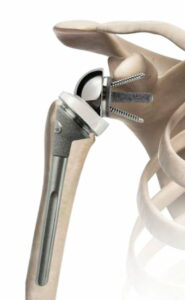

Latarjet ingreep

Deze open ingreep (met insnede van 8 tal centimeter vooraan op de schouder) wordt meestal uitgevoerd als er bijkomend een stukje bot is afgebroken van de kom of als de schouder opnieuw ontwricht na een vroeger uitgevoerde kijkoperatie. In sommige gevallen wordt dit als eerste keuze operatie uitgevoerd bv. atleten in contactsporten zoals rugby, mensen met een zwaar schouder belastend beroep.

Het voorste botuitsteeksel van het schouderblad (processus coracoïdeus) wordt losgemaakt en samen met de pezen erop getransplanteerd naar de voorzijde van de kom van de schouder (glenoid). Dit stukje bot wordt vastgezet met 2 schroeven. Het stukje bot zorgt voor een groter oppervlak van de kom, de pezen die erop vastzitten zorgen voor een bijkomende stevigheid zodat de schouder niet meer uit de kom kan.

Indien na vastgroeien van het stukje bot de schroeven hinder zouden geven kunnen die schroeven verwijderd worden.